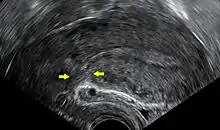

- Placenta problems (placenta praevia, placental abruption or placenta accreta)

- Umbilical cord abnormalities (vasa previa, multilobate including bilobate and succenturiate-lobed placentas, velamentous insertion)